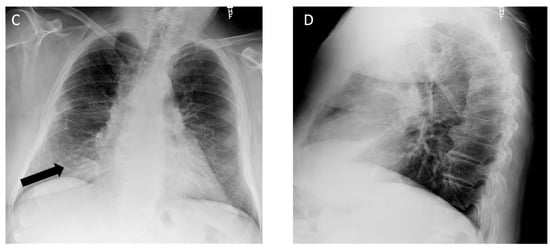

Figure 2.

A 73-year-old male with a history of remote 16 pack year smoking history and asbestos exposure as a retired plumber working on pipe and broiler insulation, diagnosed with asbestos-related pleural disease. (A) Axial computed tomography shows asbestos plaques on the right (long arrows) and diffuse pleural thickening on the left (short arrows) on the soft tissue window; (B) on the lung window, a subpleural band opacity is seen in the left lower lobe (black arrow); (C) posteroanterior view and (D) lateral view chest radiographs show diffuse pleural thickening with calcification, best appreciated by costophrenic angle blunting (black arrows).